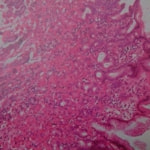

症例:炎症性ポリープ M.ダックス 10歳 オス

主訴:8ヶ月前から便が細くなり、血が混じることがある。その他、元気・食欲等、一般状態は良好。

経過:超音波検査にて直腸壁の肥厚(5㎜)が認められた。また、直腸検査で直腸全周に結節状病変を触知し、出血も確認された。消炎剤、抗生剤、整腸剤による治療への反応が長期的に悪いため、生検も含めた内視鏡検査を実施した。

内視鏡検査:肛門付近の直腸全周に、炎症および出血を伴う結節状病変を多数認めた。

病理検査:直腸の病変は、良性の非腫瘍性病変の一つである“炎症性ポリープ”と診断された。

診断後経過:炎症性ポリープは多発する傾向や腫瘍に転化する可能性があるため、消炎剤、抗生剤、整腸剤による内科療法を継続しながら、現在プルスルー法による外科的摘出術を検討中。

◎炎症性ポリープとは

近年、ミニチュアダックスで好発が知られている良性の腫瘍性の病変です。しばしば多発し、また腫瘍に転化する事があります。